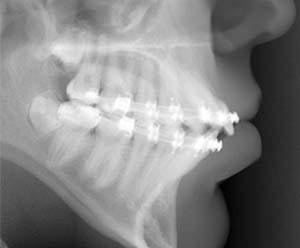

Bulard: IMTEC Corporation is well known for designing and manufacturing a wide variety of dental specialty products such as mini dental implants, root form endosseous dental implants, guided tissue and bone regeneration systems, surgical drills and instrumentation and an extensive line of implant prosthetics.

Because of IMTEC's well-known expertise in mini implants and the company's progressive outlook, orthodontists worldwide approached IMTEC requesting a mini implant adapted for orthodontic anchorage, and that is what led to IMTEC's introduction of the ORTHO Implant in 2003.

Bulard: As the popularity of IMTEC's MDI system grew, more orthodontists began to inquire about using MDI implants for anchorage purposes in their practices. This led to orthodontists using the Mini Dental Implants suggesting changes that would adapt the MDIs for orthodontic anchorage, such as a smooth surface that would not promote osseointegration. As a result, IMTEC eventually developed the ORTHO Implant.

Bulard: Extensive data on the MDI implant gave IMTEC the information necessary to ensure the ORTHO implant would be the most predictable temporary anchorage device (TAD) to date. Thorough studies were conducted by doctors at both the University of Oklahoma and Baylor University, confirming the implant's efficacy and versatility as an orthodontic anchor. Currently, research is taking place at multiple universities in the United States and abroad, and research at Baylor done by Dr. Carmen Briceno on the ORTHO Implant was just honored with the Milo Hellman Research award by the American Association of Orthodontists. Also, as more and more clinicians adopt the ORTHO Implant, valuable customer feedback is helping IMTEC continue to offer a superior product to orthodontists.

Bulard: The ORTHO Implant offers a design proven with decades of research and with more versatility than any other TAD design. The ORTHO Implant is a direct adaptation of the MDI implant design. The MDI implant went through 25 years of research and development before it was introduced to the market in 1999. Today, the MDI implant has proven to be the world's favorite and most trusted mini implant system. This is the age of evidence-based dentistry, and orthodontists should settle for nothing less than an evidence-based implant. With the ORTHO Implant, that is what they receive, and that is unique.

Versatility is the second most distinguishing characteristic of the ORTHO Implant. The system consists of one implant design, which includes an O-ball head with intersecting attachment holes, available in three different lengths as opposed to other systems that require clinicians to stock different implant designs each only useful for limited types of attachments. The fact that IMTEC developed a design that meets all attachment needs makes implant selection simpler with the ORTHO Implant than with any other TAD system, and the three different lengths facilitate placement in almost any location based on gingival thickness and bony depth.

The undercut beneath the o-ball can also be used for direct attachment of ligatures, elastics and power chains and a removable stainless steel O-cap that locks in place around the O-ball can be soldered to custom appliances or placed to prevent mucosal overgrowth and prevent patient discomfort.